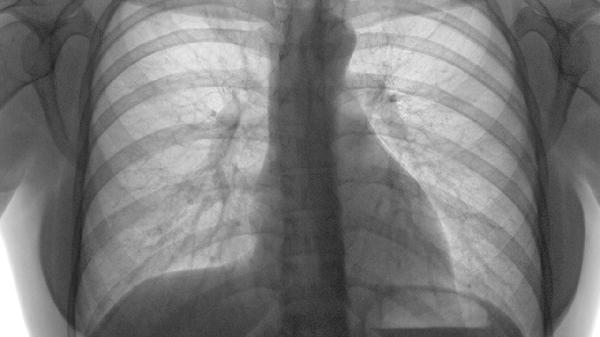

肺里查出小结节,医生却说不用治?这可能是身体在给你发"自救信号"!别急着恐慌,90%的肺结节其实都是"纸老虎",关键要看懂它们的"生存法则"。

一、肺结节为何会"黑化"成肺癌

三、这些信号要警惕

1、随访时结节增大速度超过每年2mm

2、出现分叶状、毛刺状等不规则形态

3、伴随持续性胸痛、痰中带血

4、肿瘤标志物(如CEA)进行性升高

纯磨玻璃结节进展较慢,实性成分增加要特别留意。